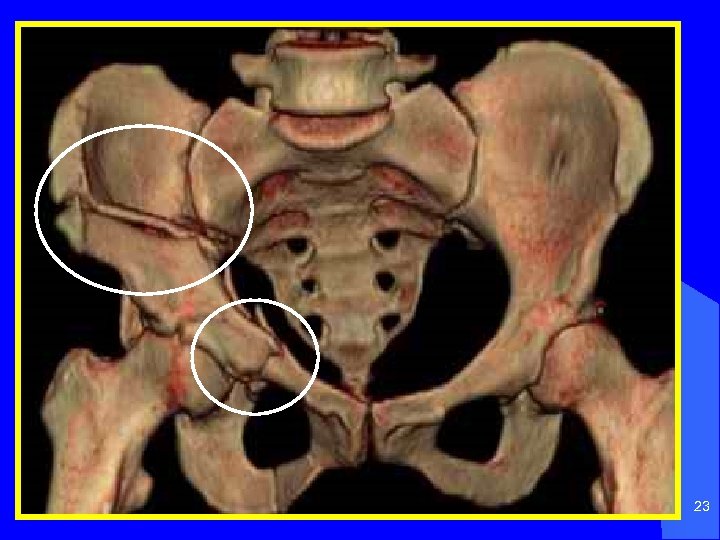

23